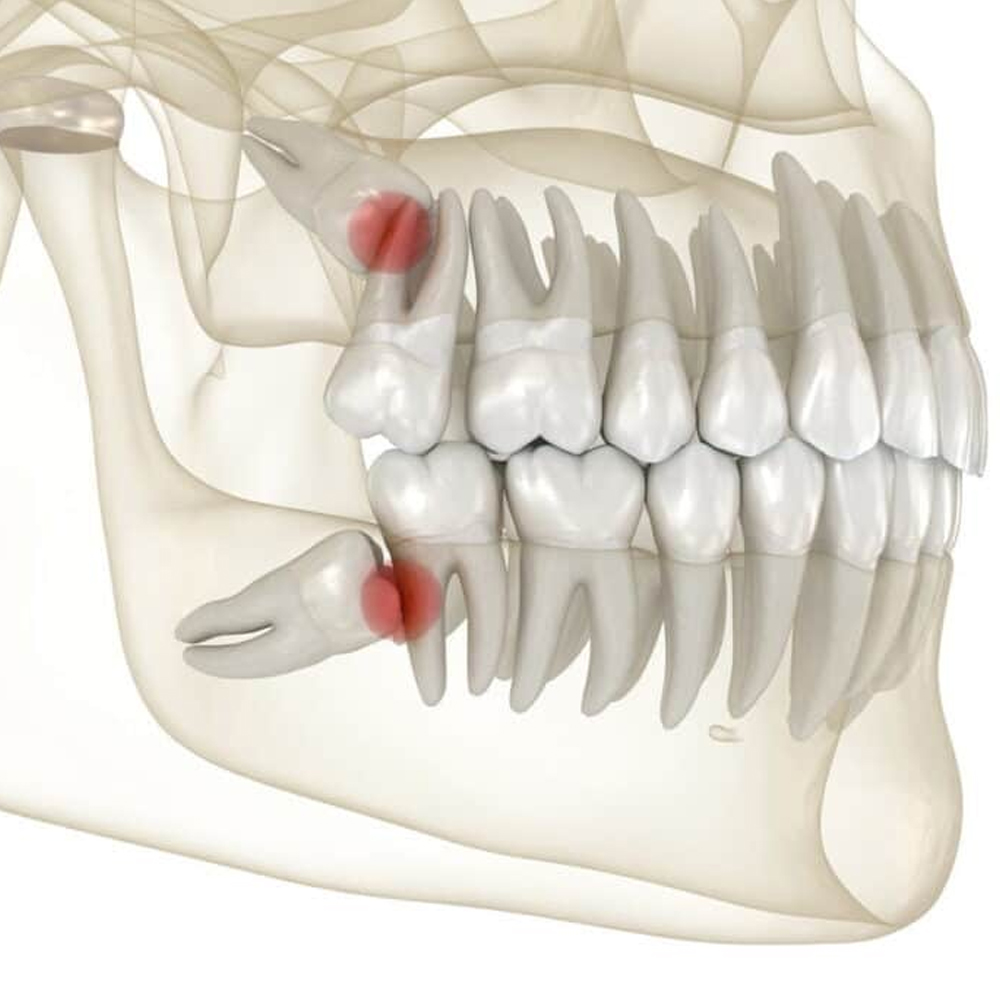

Diş Çekimi (Cerrahi) ve 20 Yaş Diş Çekimi

Normal diş çekimlerinin yanı sıra, gömülü veya sorunlu 20 yaş (akıl) dişlerinin çekimi gibi daha karmaşık cerrahi operasyonlar, deneyimli cerrahi diş hekimi kadromuz tarafından titizlikle gerçekleştirilir.

10) Gömülü 20 yaş dişim alınmalı mı?

Asemptomatik bile olsa perikoronitis, komşu diş çürüğü/rezorpsiyonu riski varsa çekim önerilebilir. CBCT ile anatomik riskler (sinir, sinüs) değerlendirilir.

Gömülü 20’lik her zaman çekilir mi? Endikasyona bağlıdır.